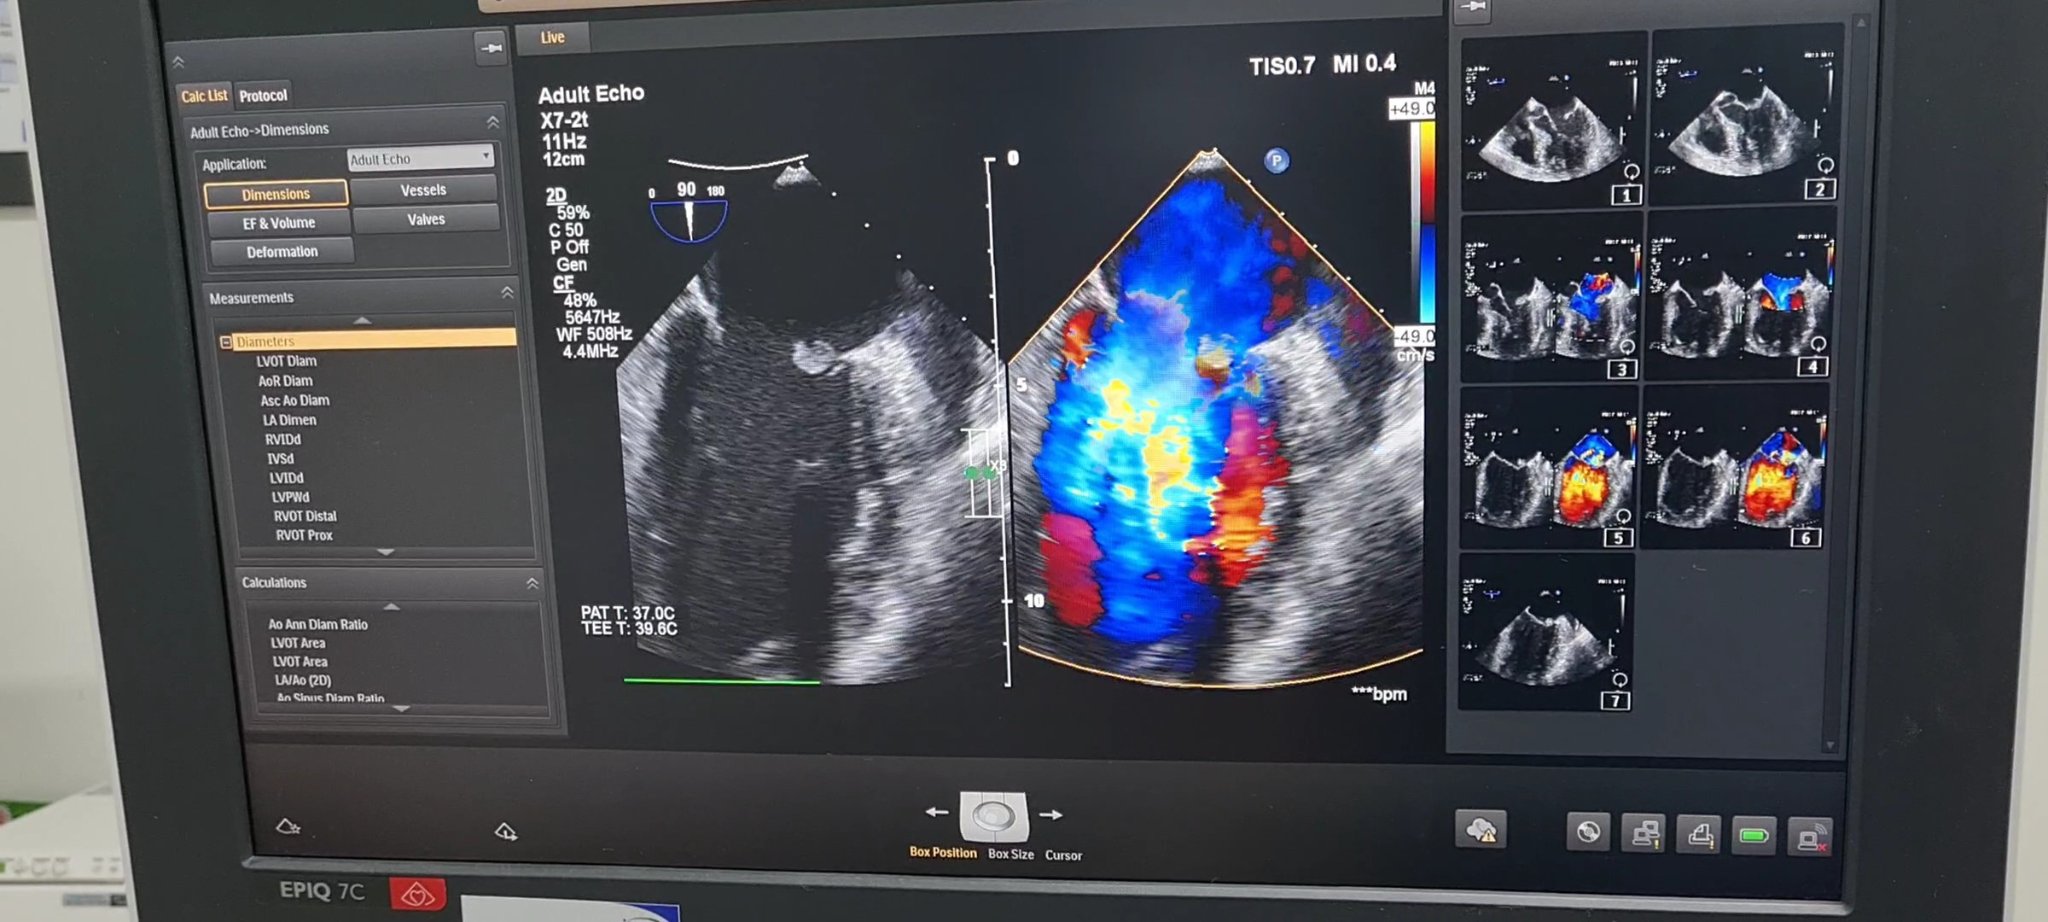

Siêu âm tim anh T. phát hiện cục sùi lớn, gây thủng van và làm hở nặng van hai lá. Ảnh: BVCC